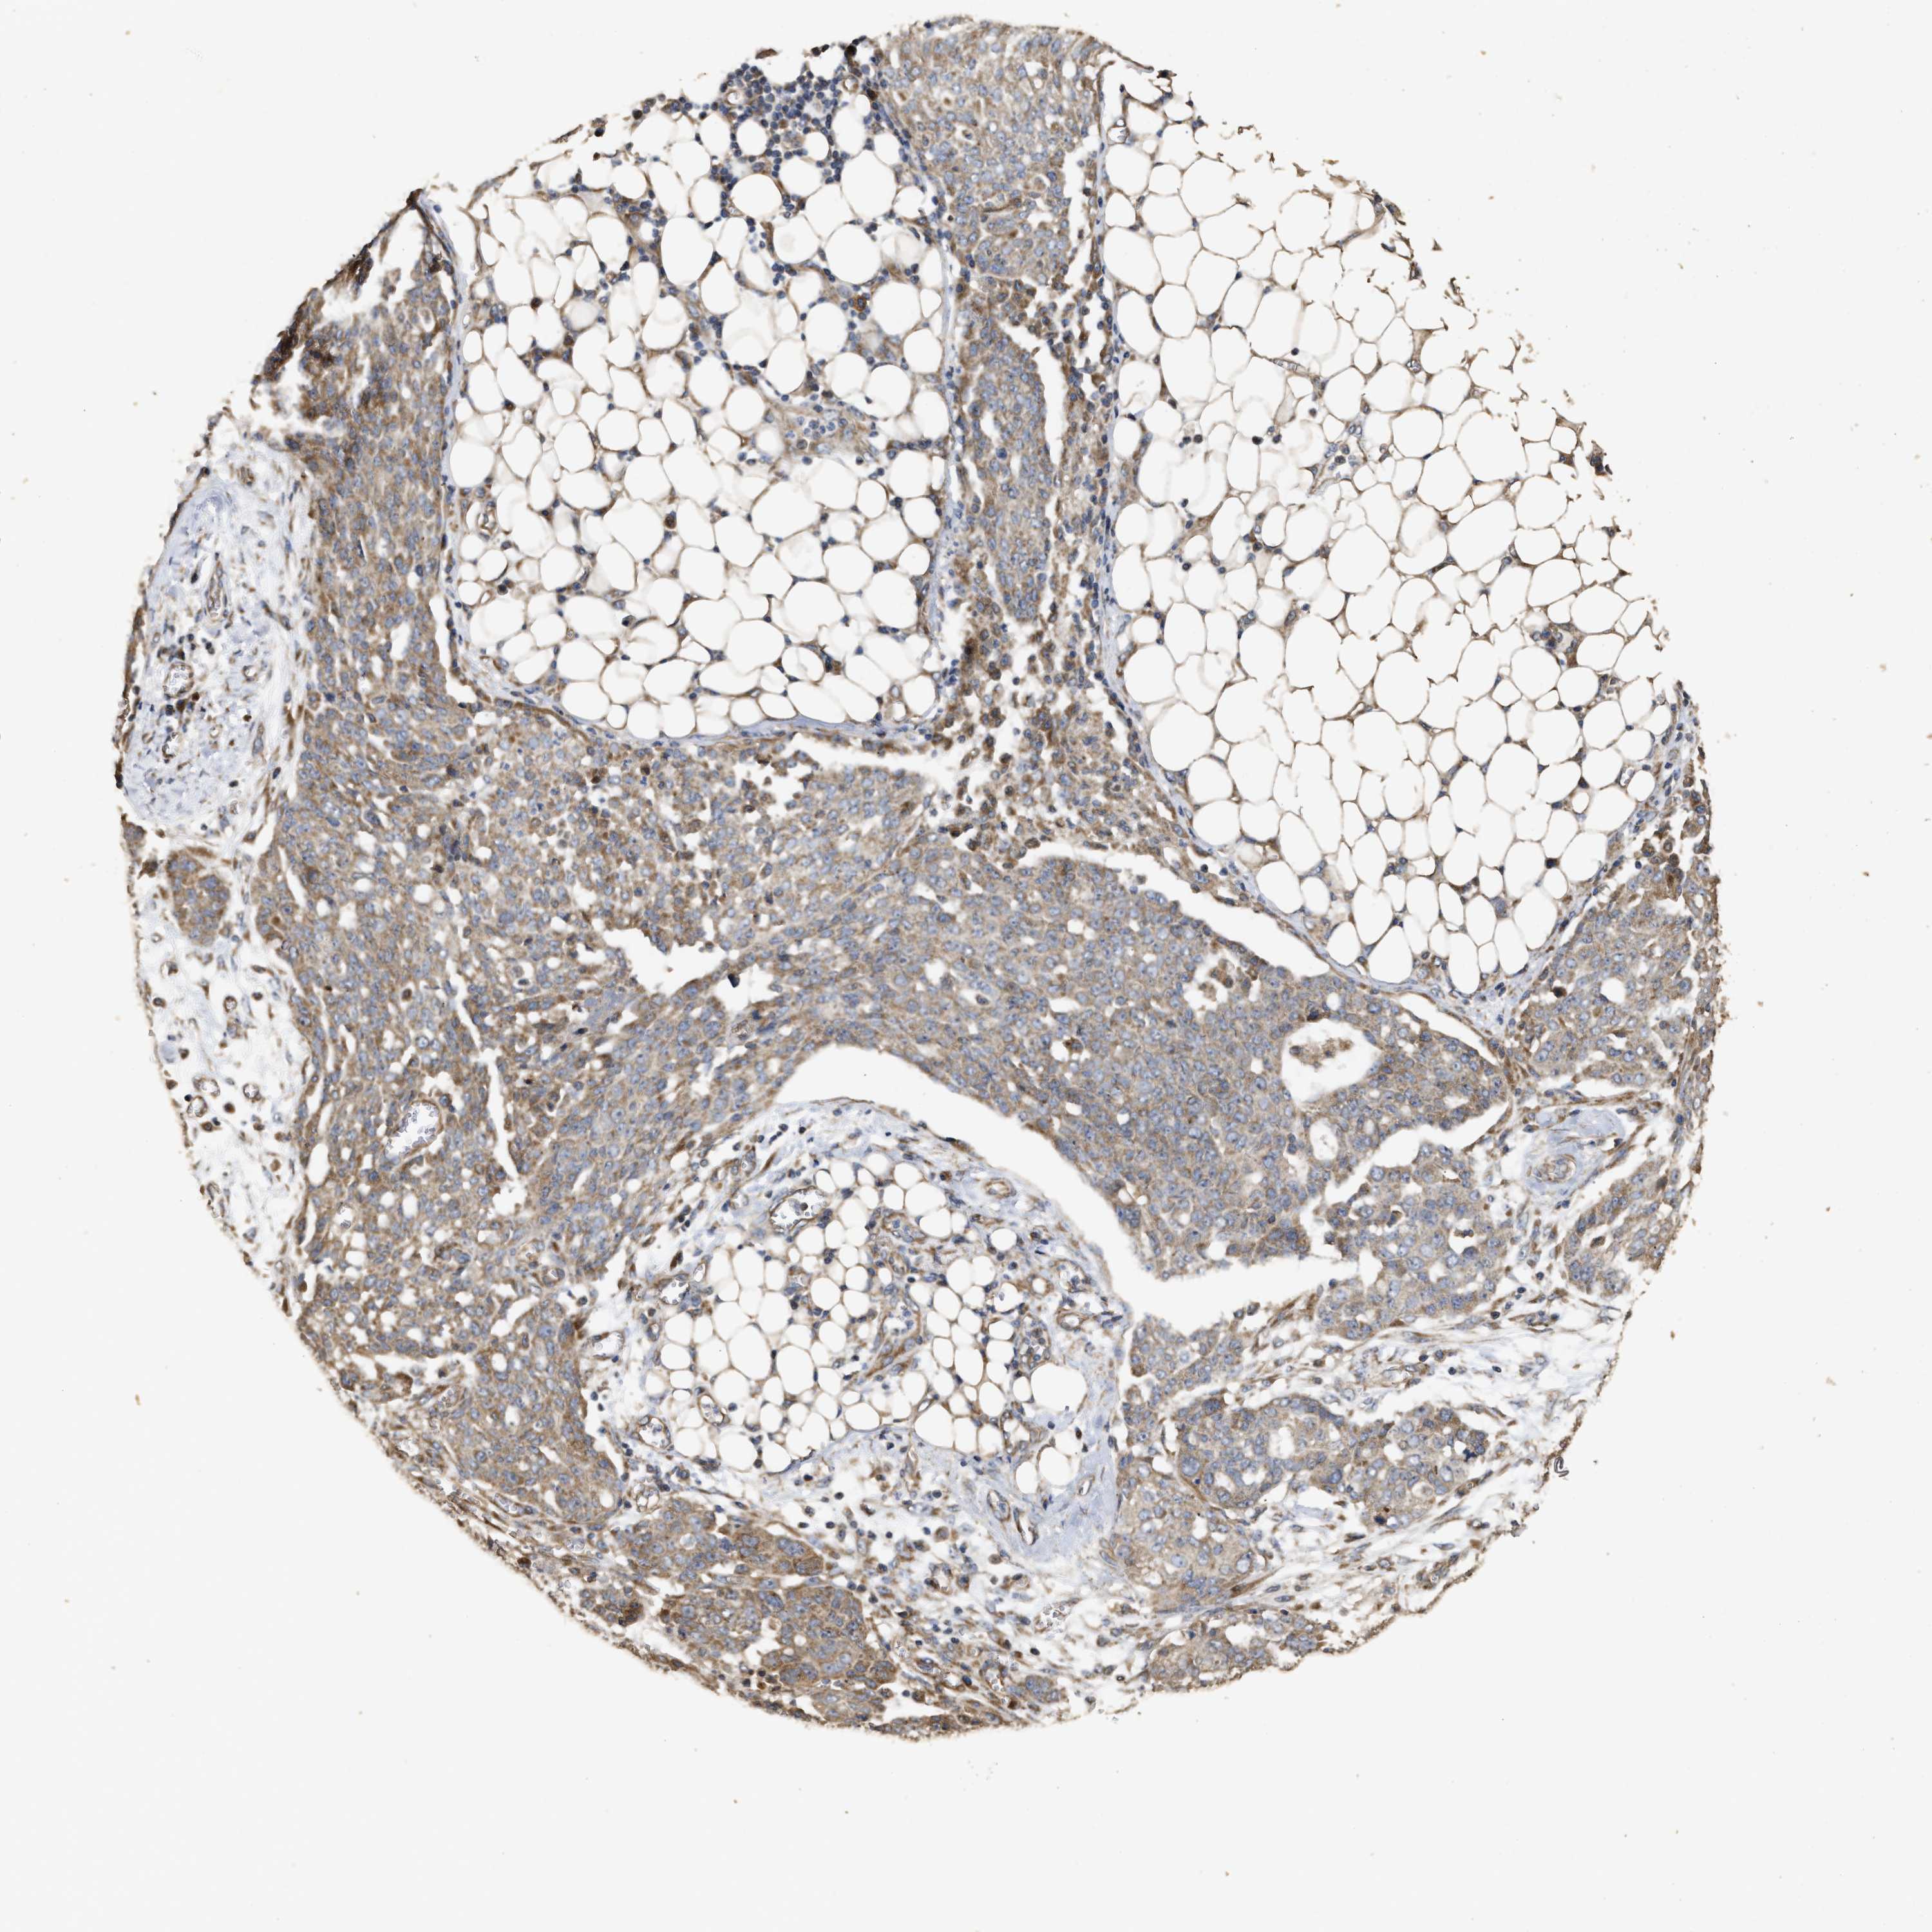

OVARIAN CANCER - Protein expressioni

A mouse-over function shows sample information and annotation data. Click on an image to view it in a full screen mode. Samples can be filtered based on level of antibody staining by selecting one or several of the following categories: high, medium, low and not detected. The assay and annotation is described here.

Note that samples used for immunohistochemistry by the Human Protein Atlas do not correspond to samples in the TCGA dataset.

Antibody stainingi

Antibody staining in the annotated cell types in the current human tissue is reported as not detected, low, medium, or high, based on conventional immunohistochemistry profiling in selected tissues. This score is based on the combination of the staining intensity and fraction of stained cells.

Each image is clickable and will lead to virtual microscopy that enables deeper exploration of all samples and also displays staining intensity scores, fraction scores and subcellular localization as well as patient and tissue information for each sample.

Antibody HPA018127

Antibody HPA027887

Antibody CAB012302

Cystadenocarcinoma, serous, NOS

Carcinoma, endometroid

Cystadenocarcinoma, mucinous, NOS

Carcinoma, NOS